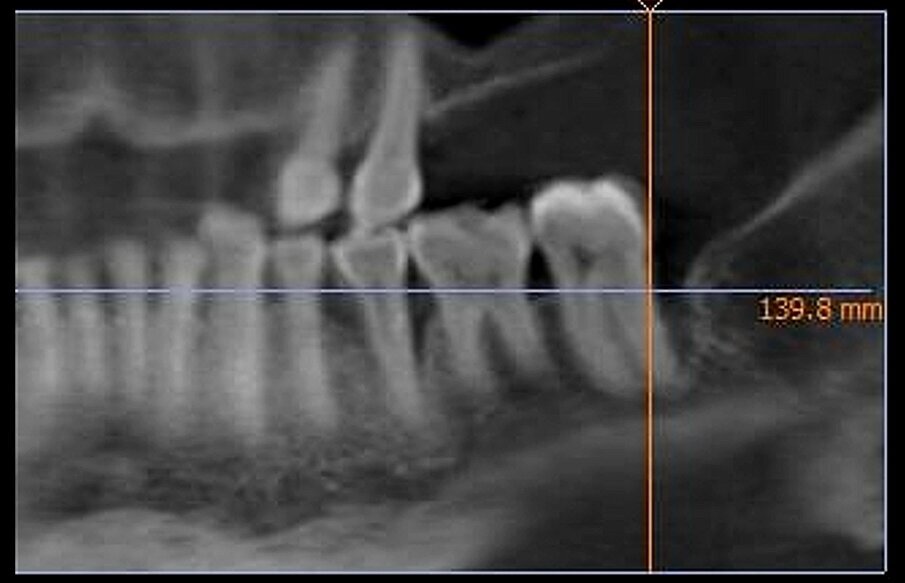

Dai sondaggi parodontali e dalle indagini radiografiche di 1° e 2° livello si evidenzia la presenza di un difetto intraosseo ampio e profondo che interessa la radice distale dell’elemento 3.7 nel suo aspetto disto-buccale; è assente il coinvolgimento della forcazione radicolare (Figg. 1-4).

Fig. 4 - RX preoperatoria che evidenzia il difetto osseo sull’elemento 3.7.

Alla baseline il valore di PPD nell’area interessata dal difetto intraosseo era pari a 8,5 mm con un indice di BoP+ mentre al momento dell’ultimo controllo (24 mesi) il valore medio di PPD era pari a 2,5 mm con un indice di BoP- con una riduzione media del valore di PPD pari a 6,0 mm. Gli esami radiografici, effettuati per mezzo di radiografie endorali periapicali, hanno confermato un sostanziale riempimento del difetto intraosseo.